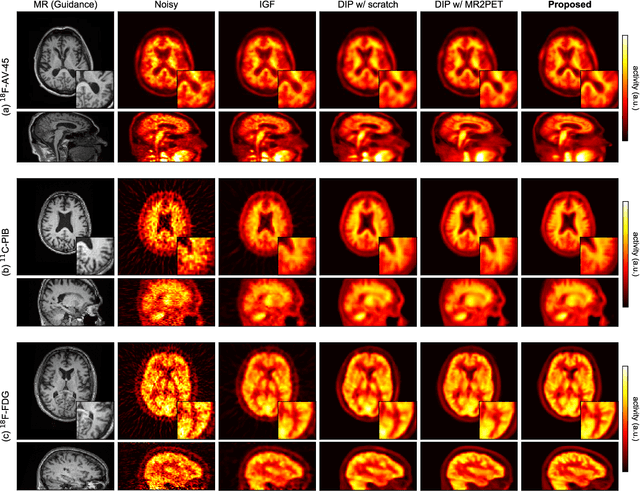

Abstract:Deep image prior (DIP) has been successfully applied to positron emission tomography (PET) image restoration, enabling represent implicit prior using only convolutional neural network architecture without training dataset, whereas the general supervised approach requires massive low- and high-quality PET image pairs. To answer the increased need for PET imaging with DIP, it is indispensable to improve the performance of the underlying DIP itself. Here, we propose a self-supervised pre-training model to improve the DIP-based PET image denoising performance. Our proposed pre-training model acquires transferable and generalizable visual representations from only unlabeled PET images by restoring various degraded PET images in a self-supervised approach. We evaluated the proposed method using clinical brain PET data with various radioactive tracers ($^{18}$F-florbetapir, $^{11}$C-Pittsburgh compound-B, $^{18}$F-fluoro-2-deoxy-D-glucose, and $^{15}$O-CO$_{2}$) acquired from different PET scanners. The proposed method using the self-supervised pre-training model achieved robust and state-of-the-art denoising performance while retaining spatial details and quantification accuracy compared to other unsupervised methods and pre-training model. These results highlight the potential that the proposed method is particularly effective against rare diseases and probes and helps reduce the scan time or the radiotracer dose without affecting the patients.